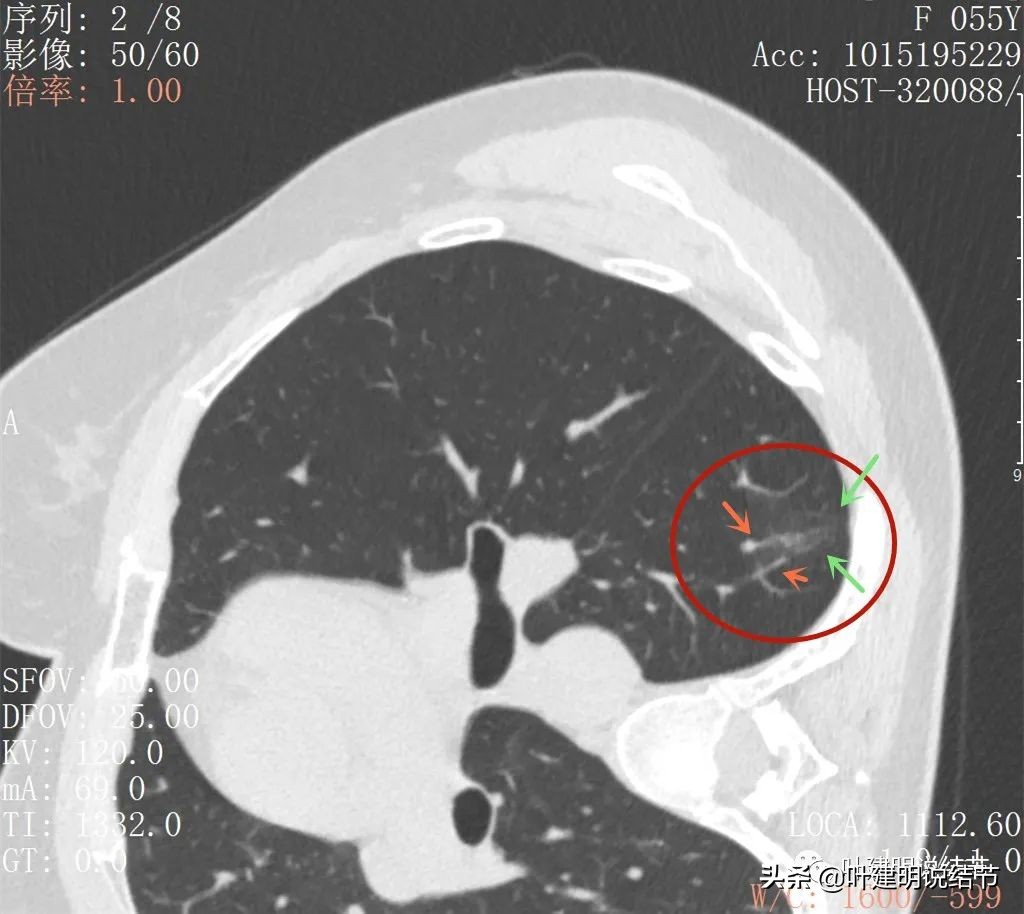

大病灶出现,密度甚淡,有血管进入的样子(桔色箭头),磨玻璃成分明显(绿色箭头),整体看,轮廓还是比较清楚的(红色箭头)

边略显模糊,主要是密度低,中间有小范围密度偏高(粉色箭头)

磨玻璃部分的密度非常淡,但轮廓相对来说还是看得清

灶内有血管穿行,表现为条状高密度,且不平整(粉色箭头),磨玻璃部分密度很淡

上图见多支血管走向病灶(桔色箭头)灶内有异常增粗血管穿行(细粉色箭头),病灶明显有磨玻璃成分,只是比较淡(绿色箭头)

病灶处有多支血管聚集的味道

边缘区密度更低的磨玻璃成分